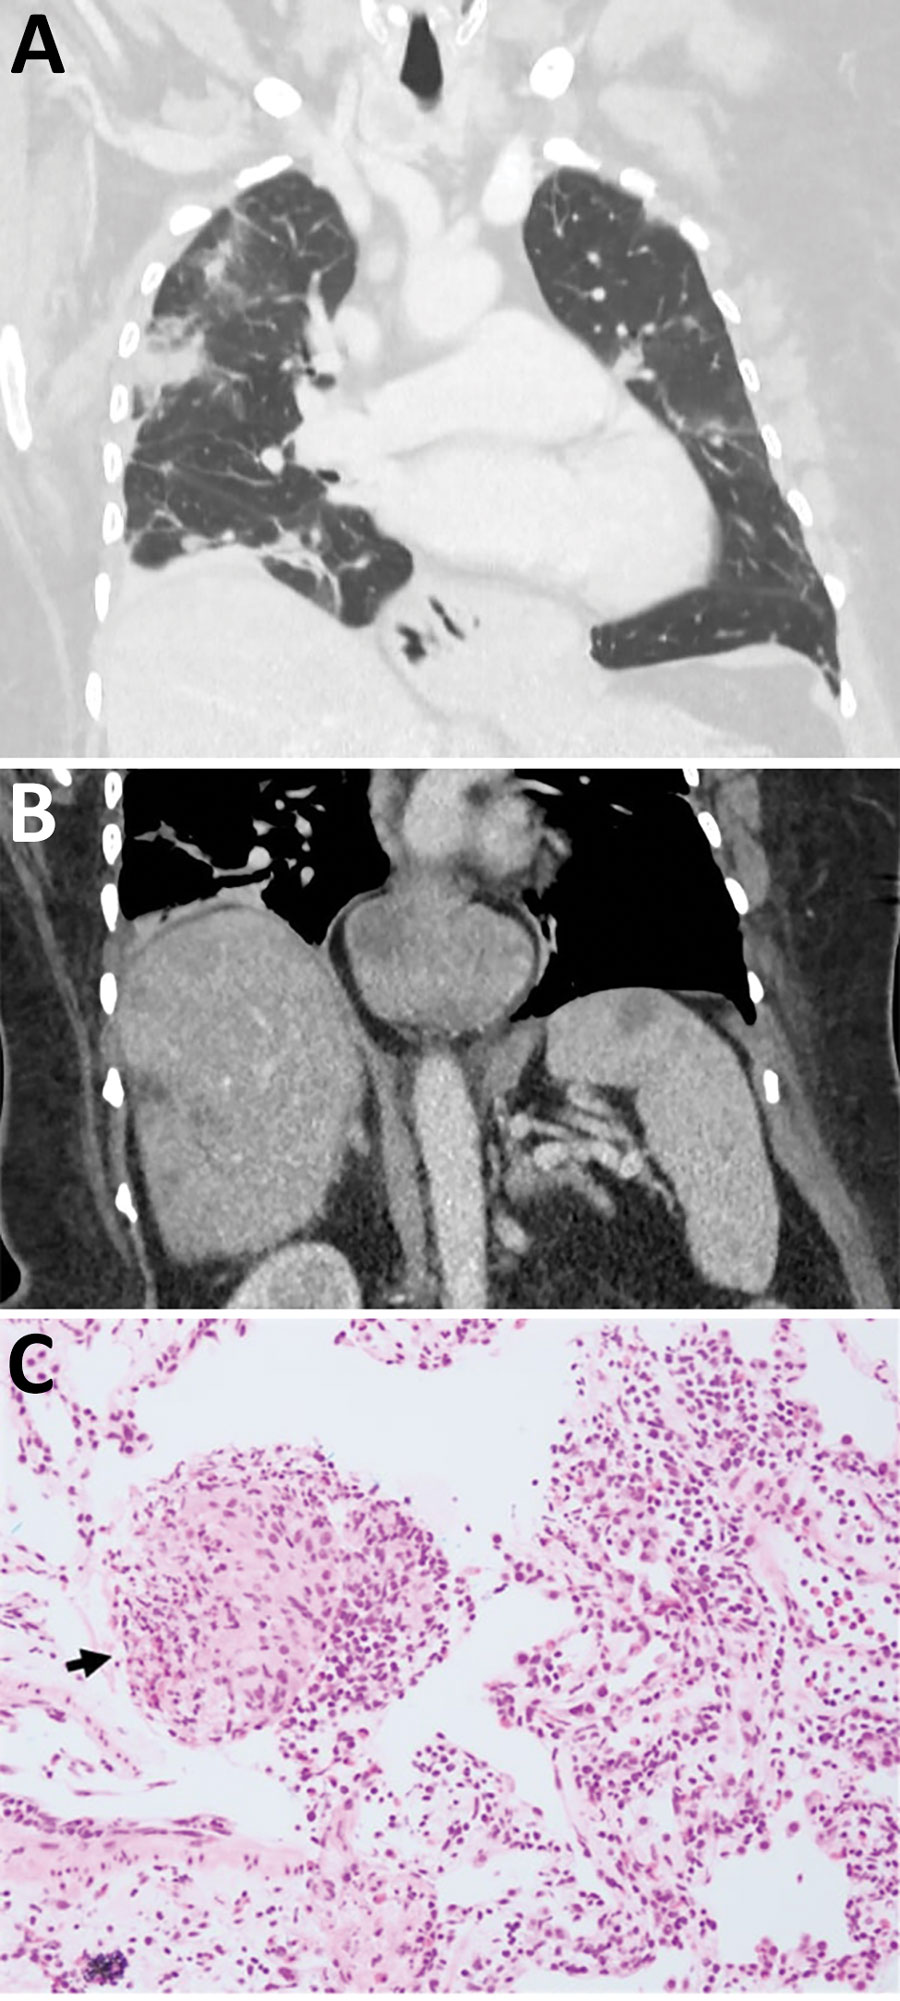

"她最初出现腹痛和腹泻,随后发烧、咳嗽和呼吸急促,"该研究的合著者之一卡琳娜-肯尼迪(Karina Kennedy)说。"现在回想起来,这些症状很可能是由于蛔虫幼虫从肠道迁移到肝脏和肺部等其他器官所致。对患者进行了呼吸道采样和肺部活检,但在这些标本中没有发现寄生虫"。

2022 年,在三个月的时间里,这名妇女开始出现健忘和抑郁加重的症状。她接受了脑部核磁共振成像检查,结果显示她的右额叶有病变,于是她接受了开放性活组织检查。就在这时,她发现了一条 3 英寸(8 厘米)长的蛔虫,并从她的大脑中拉出了这条蠕动着的蛔虫。经寄生虫学专家确认,只发现了一条蛔虫。